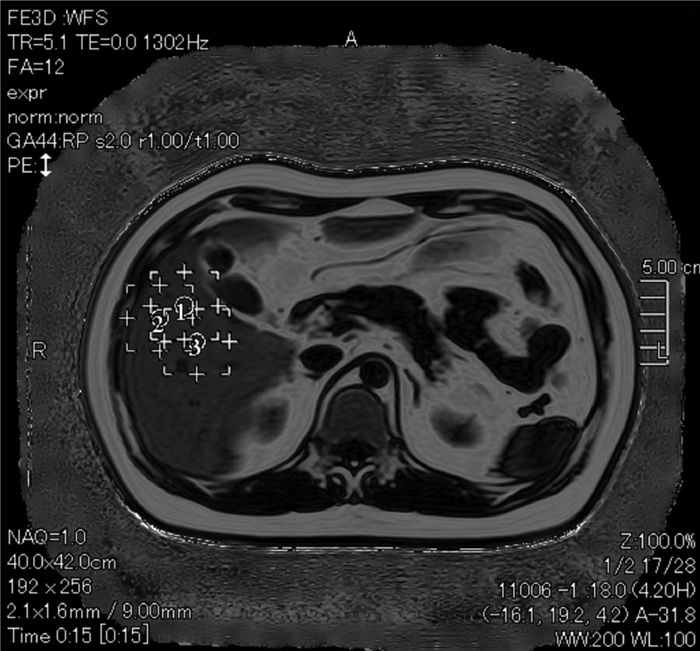

Value of magnetic resonance imaging-proton density fat fraction and FibroScan in quantitative evaluation of liver fat content in patients with chronic hepatitis B

Yiming YANG, Yupin LIU, Lixia HUANG, Zhiyuan CHEN, Shuman OUYANG, Jing PENG

2021, 37(12): 2793-2797. DOI: 10.3969/j.issn.1001-5256.2021.12.013

Abstract(1857) HTML (238) PDF (2431KB)(102)

Abstract:

Objective  To investigate the value of magnetic resonance imaging-proton density fat fraction (MRI-PDFF) and FibroScan in the quantitative evaluation of liver fat content in patients with chronic hepatitis B (CHB).  Methods  A total of 96 patients with CHB who were hospitalized in Department of Hepatology, The Second Clinical Medical College of Guangzhou University of Chinese Medicine, from February 2017 to July 2020 were enrolled, and all patients were diagnosed based on liver pathological examination. MRI-PDFF and FibroScan were performed before surgery. According to the results of liver biopsy, the patients were divided into non-fatty liver disease group with 44 patients, mild fatty liver disease group with 33 patients, and moderate-to-severe fatty liver disease group with 19 patients. A one-way analysis of variance was used for comparison of normally distributed continuous data between multiple groups, and the least significant difference t-test was used for further comparison between two groups; the Kruskal-Wallis H test was used for comparison of non-normally distributed continuous data between multiple groups, and the Mann-Whitney U test was used for further comparison between two groups; Bonferroni correction was also performed. The receiver operating characteristic (ROC) curve was plotted to analyze the area under the ROC curve (AUC) of hepatic fat fraction (HFF) and controllable attenuation parameters (CAP) in the diagnosis of fatty liver disease and obtain their sensitivities, specificities, and optimal cut-off values. The intraclass correlation coefficient was used to investigate the consistency of MRI-PDFF data.  Results  The moderate-to-severe fatty liver disease group had a significant increase in MRI-PDFF HFF compared with the non-fatty liver disease group and the mild fatty liver disease group (all P < 0.05), and the mild fatty liver disease group had a significant increase in MRI-PDFF HFF compared with the non-fatty liver disease group(P < 0.05). The moderate-to-severe fatty liver disease group had a significant increase in FibroScan CAP compared with the non-fatty liver disease group and the mild fatty liver disease group (all P < 0.05), and the mild fatty liver disease group had a significant increase in FibroScan CAP compared with the non-fatty liver disease group (P < 0.05). In the diagnosis of mild fatty liver disease, MRI-PDFF HFF had an AUC of 0.901 (P < 0.001), a sensitivity of 90.9%, and a specificity of 82.7% at the optimal cut-off value of 5.1%, and in the diagnosis of moderate-to-severe fatty liver disease, MRI-PDFF HFF had an AUC of 0.972 (P < 0.001), a sensitivity of 96.1%, and a specificity of 89.5% at the optimal cut-off value of 9.7%. In the diagnosis of mild fatty liver disease, FibroScan CAP had an AUC of 0.829 (P < 0.001), a sensitivity of 77.3%, and a specificity of 78.8% at the optimal cut-off value of 258.5 dB/m, and in the diagnosis of moderate-to-severe fatty liver disease, FibroScan CAP had an AUC of 0.830 (P < 0.001), a sensitivity of 76.6%, and a specificity of 78.9% at the optimal cut-off value of 285.5 dB/m.  Conclusion  Both MRI-PDFF and FibroScan can objectively evaluate the degree of fatty liver disease in patients with CHB. MRI-PDFF HFF and FibroScan CAP can be used as noninvasive markers for the quantitative analysis of CHB with hepatic steatosis, and MRI-PDFF HFF tends to have higher diagnostic efficiency.